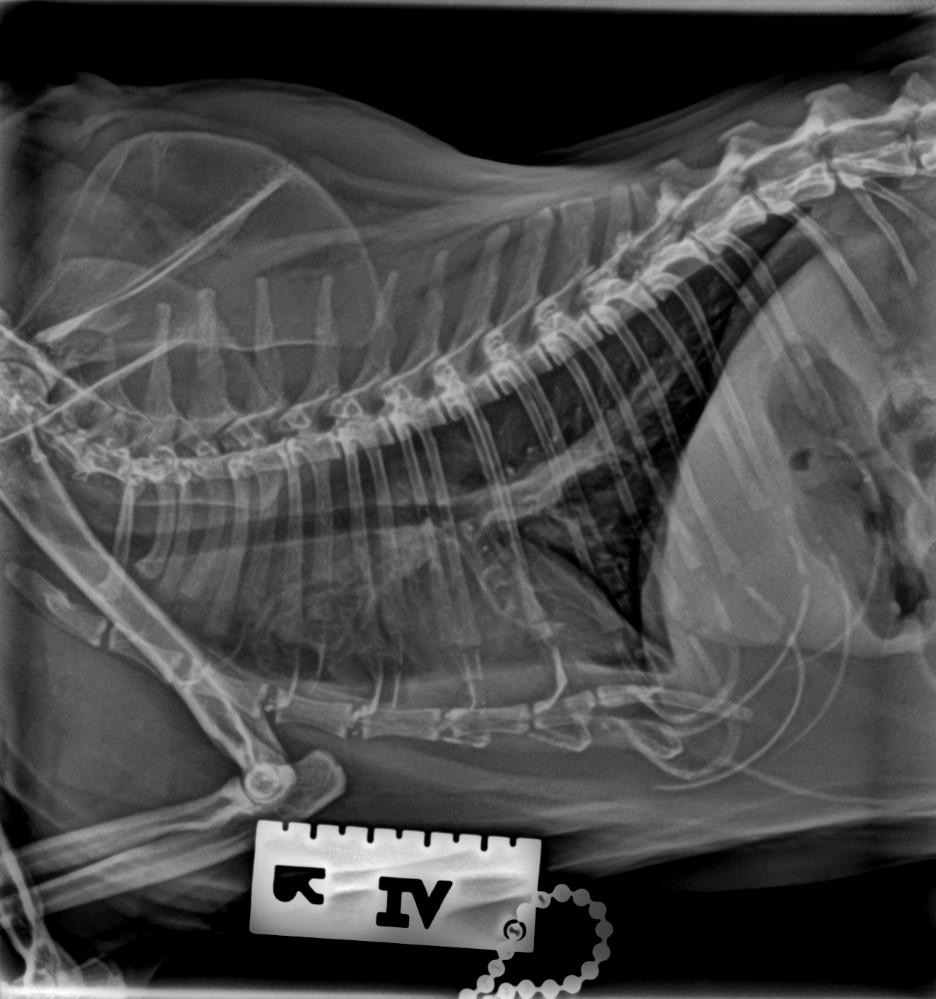

개구호흡과 컥컥거리는게 피토하는거보다 위험해보인다고 엑스레이를 찍자고하길래 찍었어요.

그런데 의사소견으로 폐에 물이 차 보인다는거에요. 당장 응급실로 가보라고...

근데 솔직히 엥? 싶긴했어요. 그건 아닌거같았거든요. 보호자로서 볼때..

제가볼땐 호흡문제보다 피토가 더 문제라고 생각했는데,

폐에 물찬거 80퍼센트정도 장담한다고 하더라구요.